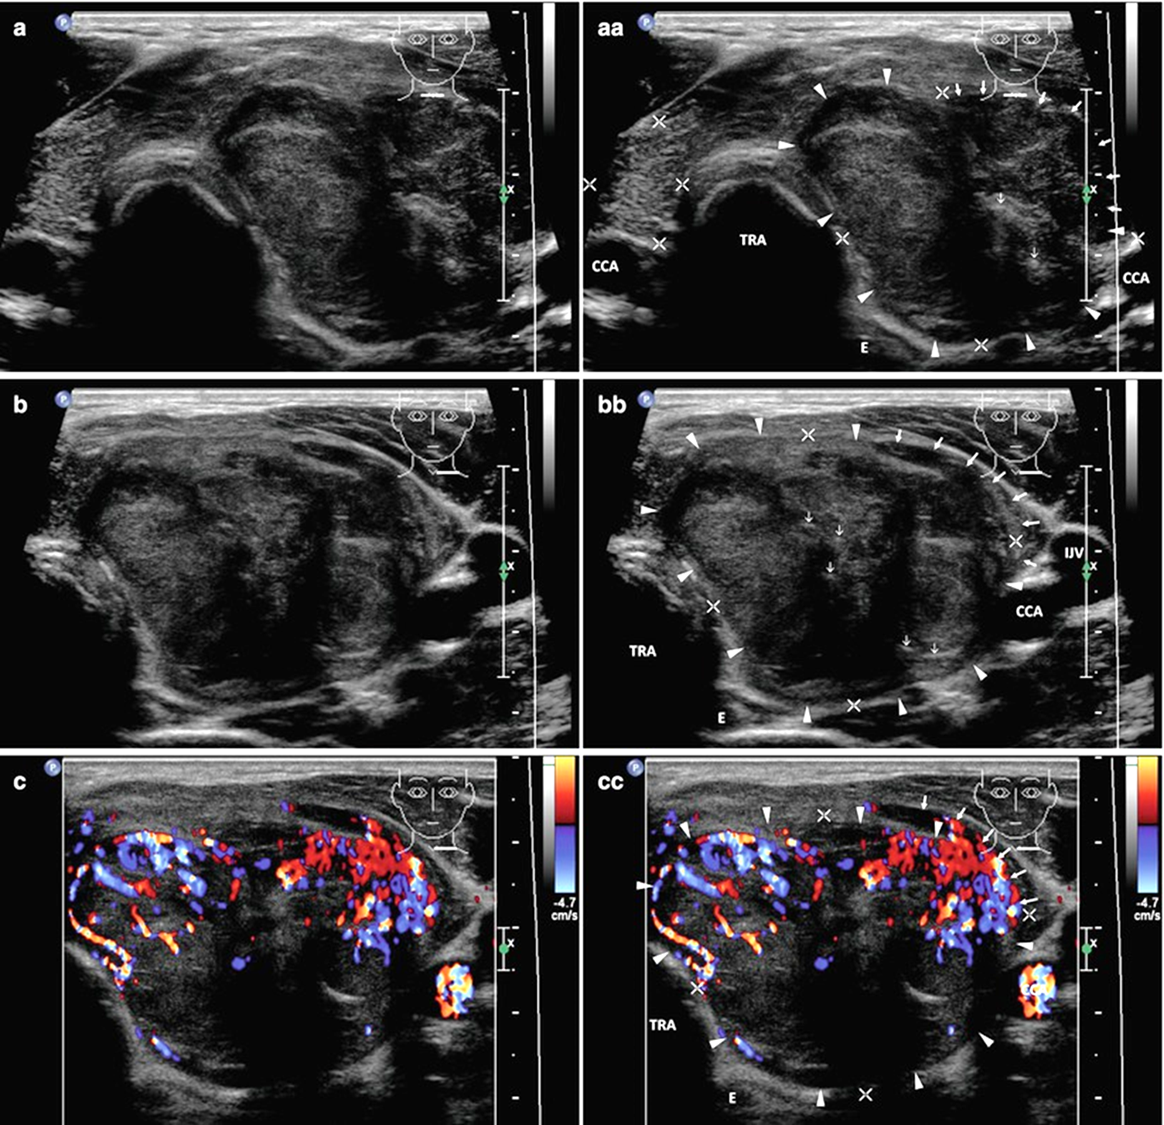

Анапластический рак щитовидной железы при УЗИ

• Обычно визуализируется крупное диффузно-неоднородное бесформенное гипоэхогенное образование, занимающее всю долю, без четких границ.

• В 78% случаев наблюдаются зоны некроза опухоли, в 58% случаев - кальцинаты.

• В 47% случаев опухолевые узлы АР ЩЖ окружены зонами узловой гиперплазии.

• Как правило, опухоли хорошо васкуляризированы за исключением зон некроза.

• Отмечается, что в момент исследования опухоль обычно находится в уже далеко зашедшей клинической стадии и распространяется практически на всю ткань железы.

• Экстракапсулярное распространение с инфильтрацией трахеи, пищевода, мягких тканей шеи наблюдается в 30% случаев; может быть тромбоз внутренней яремной вены и опухолевая окклюзия общей сонной артерии.

• В 80% случаев наблюдаются метастазы в регионарные лимфоузлы в виде увеличенных гипоэхогенных образований округлой или овальной формы на стороне локализации новообразования, реже на противоположной.